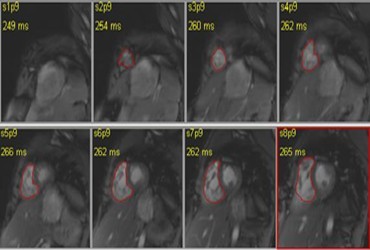

MRI of right ventricle

MRI contours of Right Ventricle

In turn, RV dilatation can evolve into irreversible RV myocardial contractile dysfunction, and has been related to sudden death in many “repaired TOF” patients. To normalize RV loading conditions, pulmonary valve replacement is often necessary and should be performed prior to the onset of irreversible RV myocardial damage. In this study we try to understand the performance of the right ventricle of the heart and the pulmonary arterial blood flow using Computational Fluid Dynamics and Fluid Structure Interactions study on patient specific data.